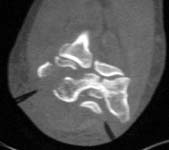

Images are of 59 yo female with low, comminuted distal humerus fx with fragments free posteriorly, high degree of comminution laterally plus involvement of the medial condyle.

at 59 years old, i would opt for ORIF. i would use a posterior approach with olecranon osteotomy - double plating with plates perpendicular to each other - with the goal being anatomic restoration and stable fixation for early motion to minimize stiffness. It is hard to say more since I would want to see more of the radiographic studies for preoperative planning. (ie, at least the AP x-ray, and probably at least a few more of the CT images). From what I can see, i think the main fragments are large enough for stable fixation. If not, the fixation might need supplementation with one of the hinged external fixators. i think the large anterior fragment seen on the lateral view is the capitellum and it would have to be retrieved. i think it would be possible with the posterior approach, but that is where access to more imaging would be helpful.